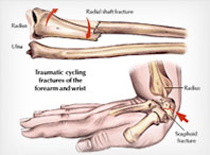

There are several different ways in which a bone can fracture; for example a clean break to the bone that does not damage surrounding tissue or tear through the skin is known as a closed fracture or a simple fracture. On the other hand, one that damages surrounding skin or tissue is known as a compound fracture or an open fracture. Compound or open fractures are generally more serious than simple fractures, with a much higher risk of infection.

Treatment depends on the type of fracture, its severity, the individual's age, and the person's general health. The first priority in treating any fracture is to address the entire medical status of the patient.

Fractures are treated in a variety of ways. The intention of most treatments is to realign the fractured bones in their original orientation and then to eliminate movement so the bones can heal. Realignment of the bone pieces in a fracture is known as Reduction of the fracture.

Many fractures require surgery to repair. Though surgery comes with its own risks, modern orthopedic techniques can lead to improved outcomes. The surgical technique used will depend on the nature of the specific fracture. Some of these techniques include:

What are the potential complications of fractures?

Fractures can range from mild to severe and can result in almost no complications or can result in serious complications. The causeof the fracture, the location of the fracture, and the way the fracture is treated will all affect the potential complications.